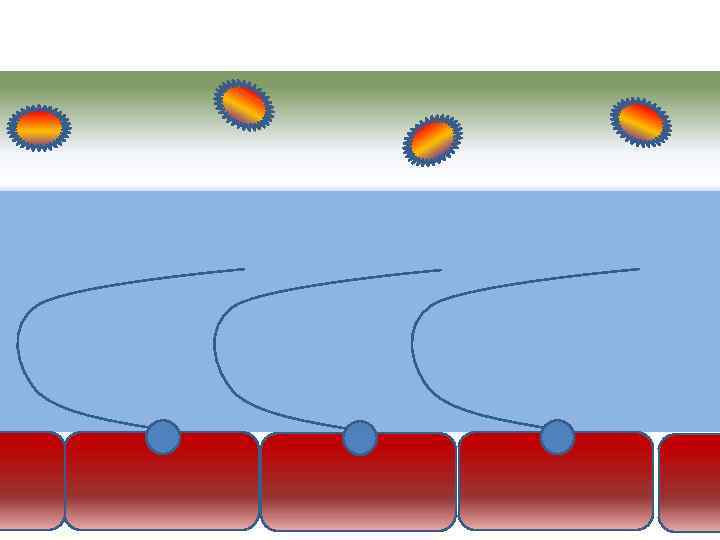

Движение клеток реснитчатого эпителия Движение вперед 1 – 3 Обратное движение 4 – 8

Движение клеток реснитчатого эпителия Движение вперед 1 – 3 Обратное движение 4 – 8

Механизм защиты легкого Слизь (зеленый цвет) нейтрализует и связывает патогенную флору(синий цвет) Слизь – это барьер между клетками и патогенной флорой Слизь – это транспортное средство

Механизм защиты легкого Слизь (зеленый цвет) нейтрализует и связывает патогенную флору(синий цвет) Слизь – это барьер между клетками и патогенной флорой Слизь – это транспортное средство